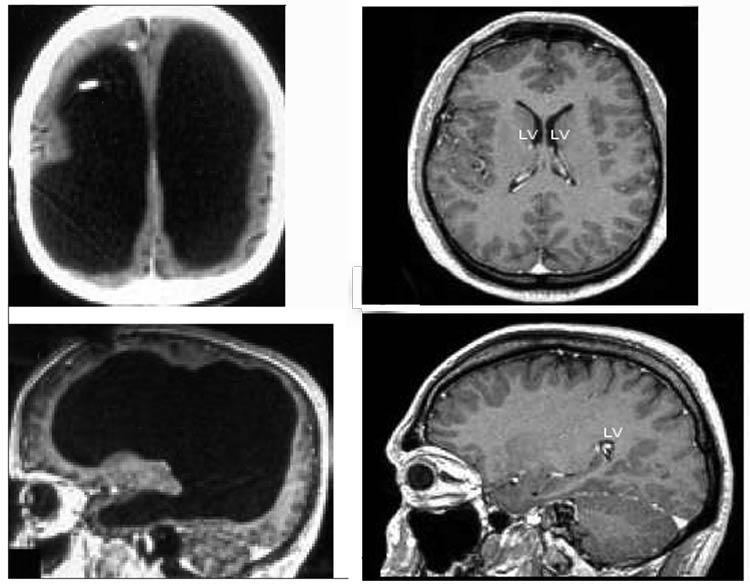

fransa'da beyninin %90'ı olmadan yaşayan bir adam hayatına sorunsuzca devam ediyor. geçirdiği bir rahatsızlığın ardından beyninin %90'ını kaybeden adamın ıq'su 75 ve devlet memurluğu görevini sorunsuzca sürdürüyor.

(bkz: hidrosefali) halk arasında beyinde su toplanması olarak da bilinir. çocuklukta gelişen hidrosefaliye adapte olmuş bir beyne sahip adamdır. ani gelişen hidrosefaliye beyin adapte olamaz ve herniasyon dediğimiz durum gerçekleşir.

beyin sapı yani beynin solunum merkezi gibi hayati bölgelerini içeren kısım basınç etkisiyle omuriliğe doğru kayar ve sıkışır. sonucu ani koma ve dakikalar içinde müdahale edilmezse ölümdür. kronik hidrosefalinin klinik triadında idrar inkontinansı(idrar kaçırma), unutkanlık, yürürken denge problemleri görülür. hasta, masabaşı çok fazla sorumluluğu olmayan bi işte çalışabilir. ülkemizde olsa bunun 10da 1i bir rahatsızlıkla sağlık kuruluna başvurup ya malulen emekli olur ya da bakım parası falan bağlatır. hangi parti muhabbetine diğer arkadaşlar değinmiştir. esen kalın.

(bkz: hidrosefali)

(bkz: hidranensefali)

beyinsiz yaşanabilir mi diye merak edenler için ise bir bilgide ben vereyim ;

anensefali nadir görülen ciddi bir doğum anomalsidir. yenidoğanın kafatası ve beyin gelişimi yetersizdir. anensefali, döllenmeden sonraki 23-26'ıncı günler arasında nöral tüpün başka yakın kısmındaki kapanma bozukluğu sonucu ortaya çıkan ve beyin, kafatası ve kafatası derisinin büyük bir kısmının yokluğu olarak tanımlanabilir.

beyni olmadan doğan çocuklar en fazla 3 3 gün yaşamalarına ya da ölü doğmalarına rağmen,

abd'nin colorado eyaletinin pueblo kentinde beyni olmadan doğan nickolas coke isimli çocuk herhangi bir makinaya bağlı kalmaksızın 3 yıl yaşamıştır....